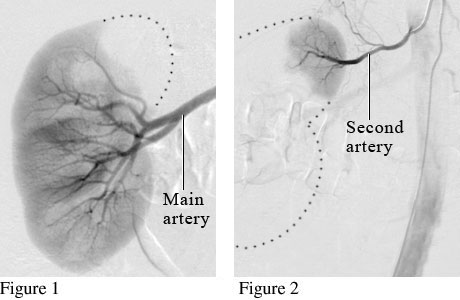

Angiogram of a Normal Kidney

Many people have more than one artery for blood flow to the kidneys. Figure 1 is an angiogram showing the main artery supplying blood flow to the kidney. Figure 2 is an angiogram showing a second artery helping to supply blood to the kidney.